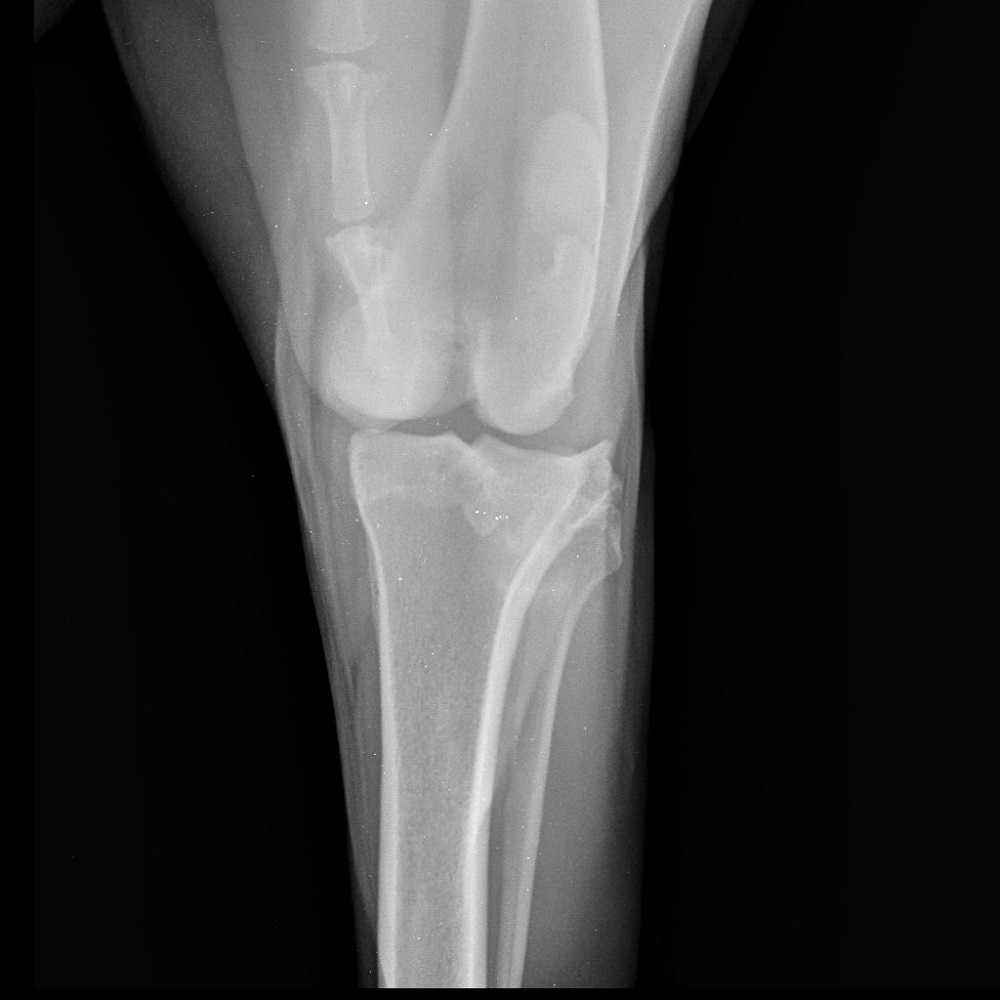

Прямая проекция коленного сустава у алабая при хроническом течении разрыва ПКС